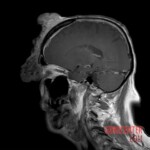

At the hospital, he presented with a large, foul-smelling mass with chronic bleeding, which blocked his right eye and caused significant eyelid swelling. Imaging revealed a malignant mass invading the skull and frontal sinus, along with a separate mass above the right parotid gland. Biopsy confirmed squamous cell carcinoma.

The patient received blood transfusions, stabilizing his condition. Further examinations showed no metastases. Doctors recommended surgical removal of as much of the facial and parotid mass as possible, followed by radiotherapy and immunotherapy. The right eye will likely need to be removed, and the patient will lose function of the right facial nerve, resulting in permanent drooping of the right side of his face.